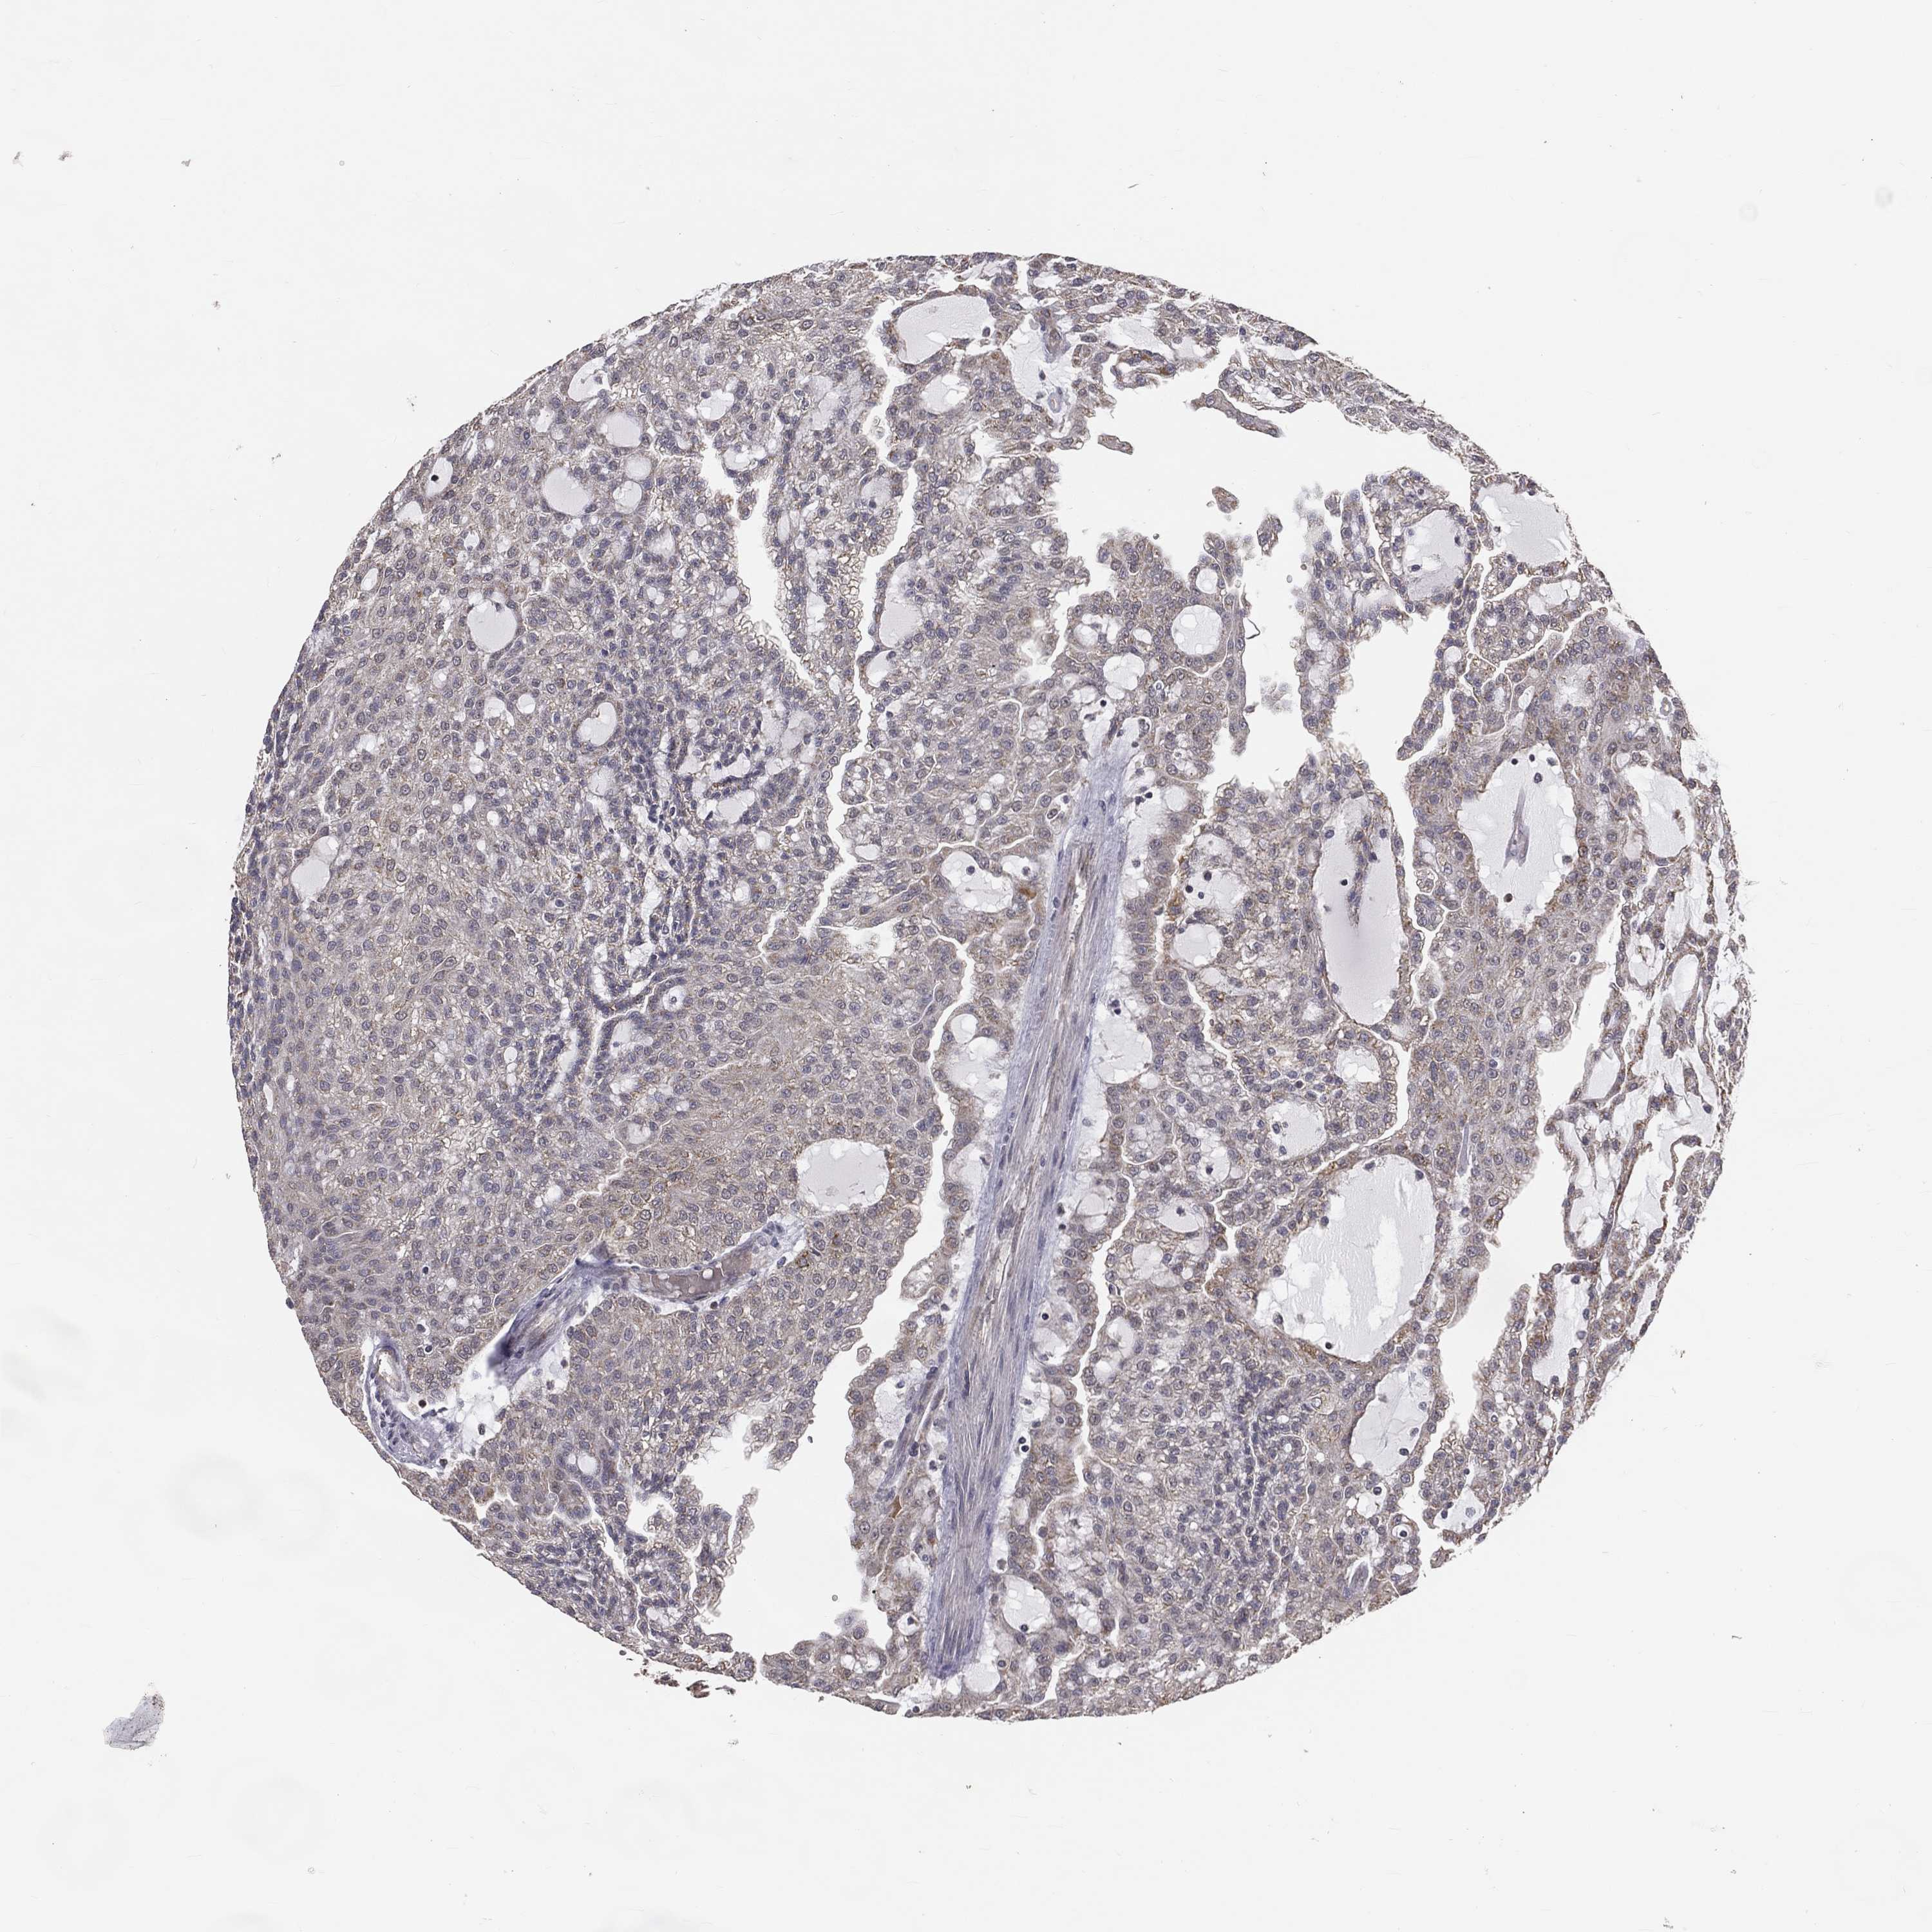

KIDNEY RENAL CLEAR CELL CARCINOMA (VALIDATION) - Interactive survival scatter ploti

The Survival Scatter plot shows the clinical status (i.e. dead or alive) for all individuals in the patient cohort, based on the same data that underlies the corresponding Kaplan-Meier plots. Patients that are alive at last time for follow-up are shown in blue and patients who have died during the study are shown in red.

The x-axis shows the expression levels (FPKM) of the investigated gene in the tumor tissue at the time of diagnosis. The y-axis shows the follow-up time after diagnosis (years). Both axes are complimented with kernel density curves demonstrating the data density over the axes. The top density plot shows the expression levels (FPKM) distribution among dead (red) and alive patients (blue). The right density plot shows the data density of the survived years of dead patients with high and low expression levels respectively, stratified using the cutoff indicated by the vertical dashed line through the Survival Scatter plot. This cutoff is automatically defined based on the FPKM cutoff that minimizes the p-score. The cutoff can be changed by dragging the vertical line or by entering a cutoff value in the square labeled "Current cut-off".

Under the Survival Scatter plot the p-score landscape (black curve; left axis) is shown together with dead median separation (red curve; right axis). Dead median separation is the difference in median mRNA expression between patients who have died with high and low expression, respectively. It is calculated as follows: median FPKM expression of dead patients with high expression - median FPKM expression of dead patients with low expression. This is intended to aid the user in visually exploring custom cutoffs and the associated p-scores and dead median separation.

& Survival analysisi

Kaplan-Meier plots summarize results from analysis of correlation between mRNA expression level and patient survival. Patients were divided based on level of expression into one of the two groups "low" (under cut off) or "high" (over cut off). X-axis shows time for survival (years) and y-axis shows the probability of survival, where 1.0 corresponds to 100 percent.

MRPL46 is validated prognostic, high expression is favorable in Kidney Renal Clear Cell Carcinoma (validation)

Best expression cut offi

Based on the FPKM value of each gene, patients were classified into two groups and association between prognosis (survival) and gene expression (FPKM) was examined. The best expression cut-off refers the FPKM value that yields maximal difference with regard to survival between the two groups at the lowest log-rank P-value. Best expression cut-off was selected based on survival analysis .

When clicking on this number, the vertical dashed line indicating cut-off, the interactive survival plot, and the Kaplan-Meier curve will be adjusted to show results based on the best expression cut-off.

: 29.85

TCGA RNA samplesi

RNA-seq data is reported as average FPKM (number Fragments Per Kilobase of exon per Million reads), generated by the The Cancer Genome Atlas (TCGA) .

Normal distribution across the dataset is visualized with box plots, shown as median and 25th and 75th percentiles. Points are displayed as outliers if they are above or below 1.5 times the interquartile range. FPKM values of the individual samples are presented next to the box plot.

Average pTPM 30.3

Number of samples 100